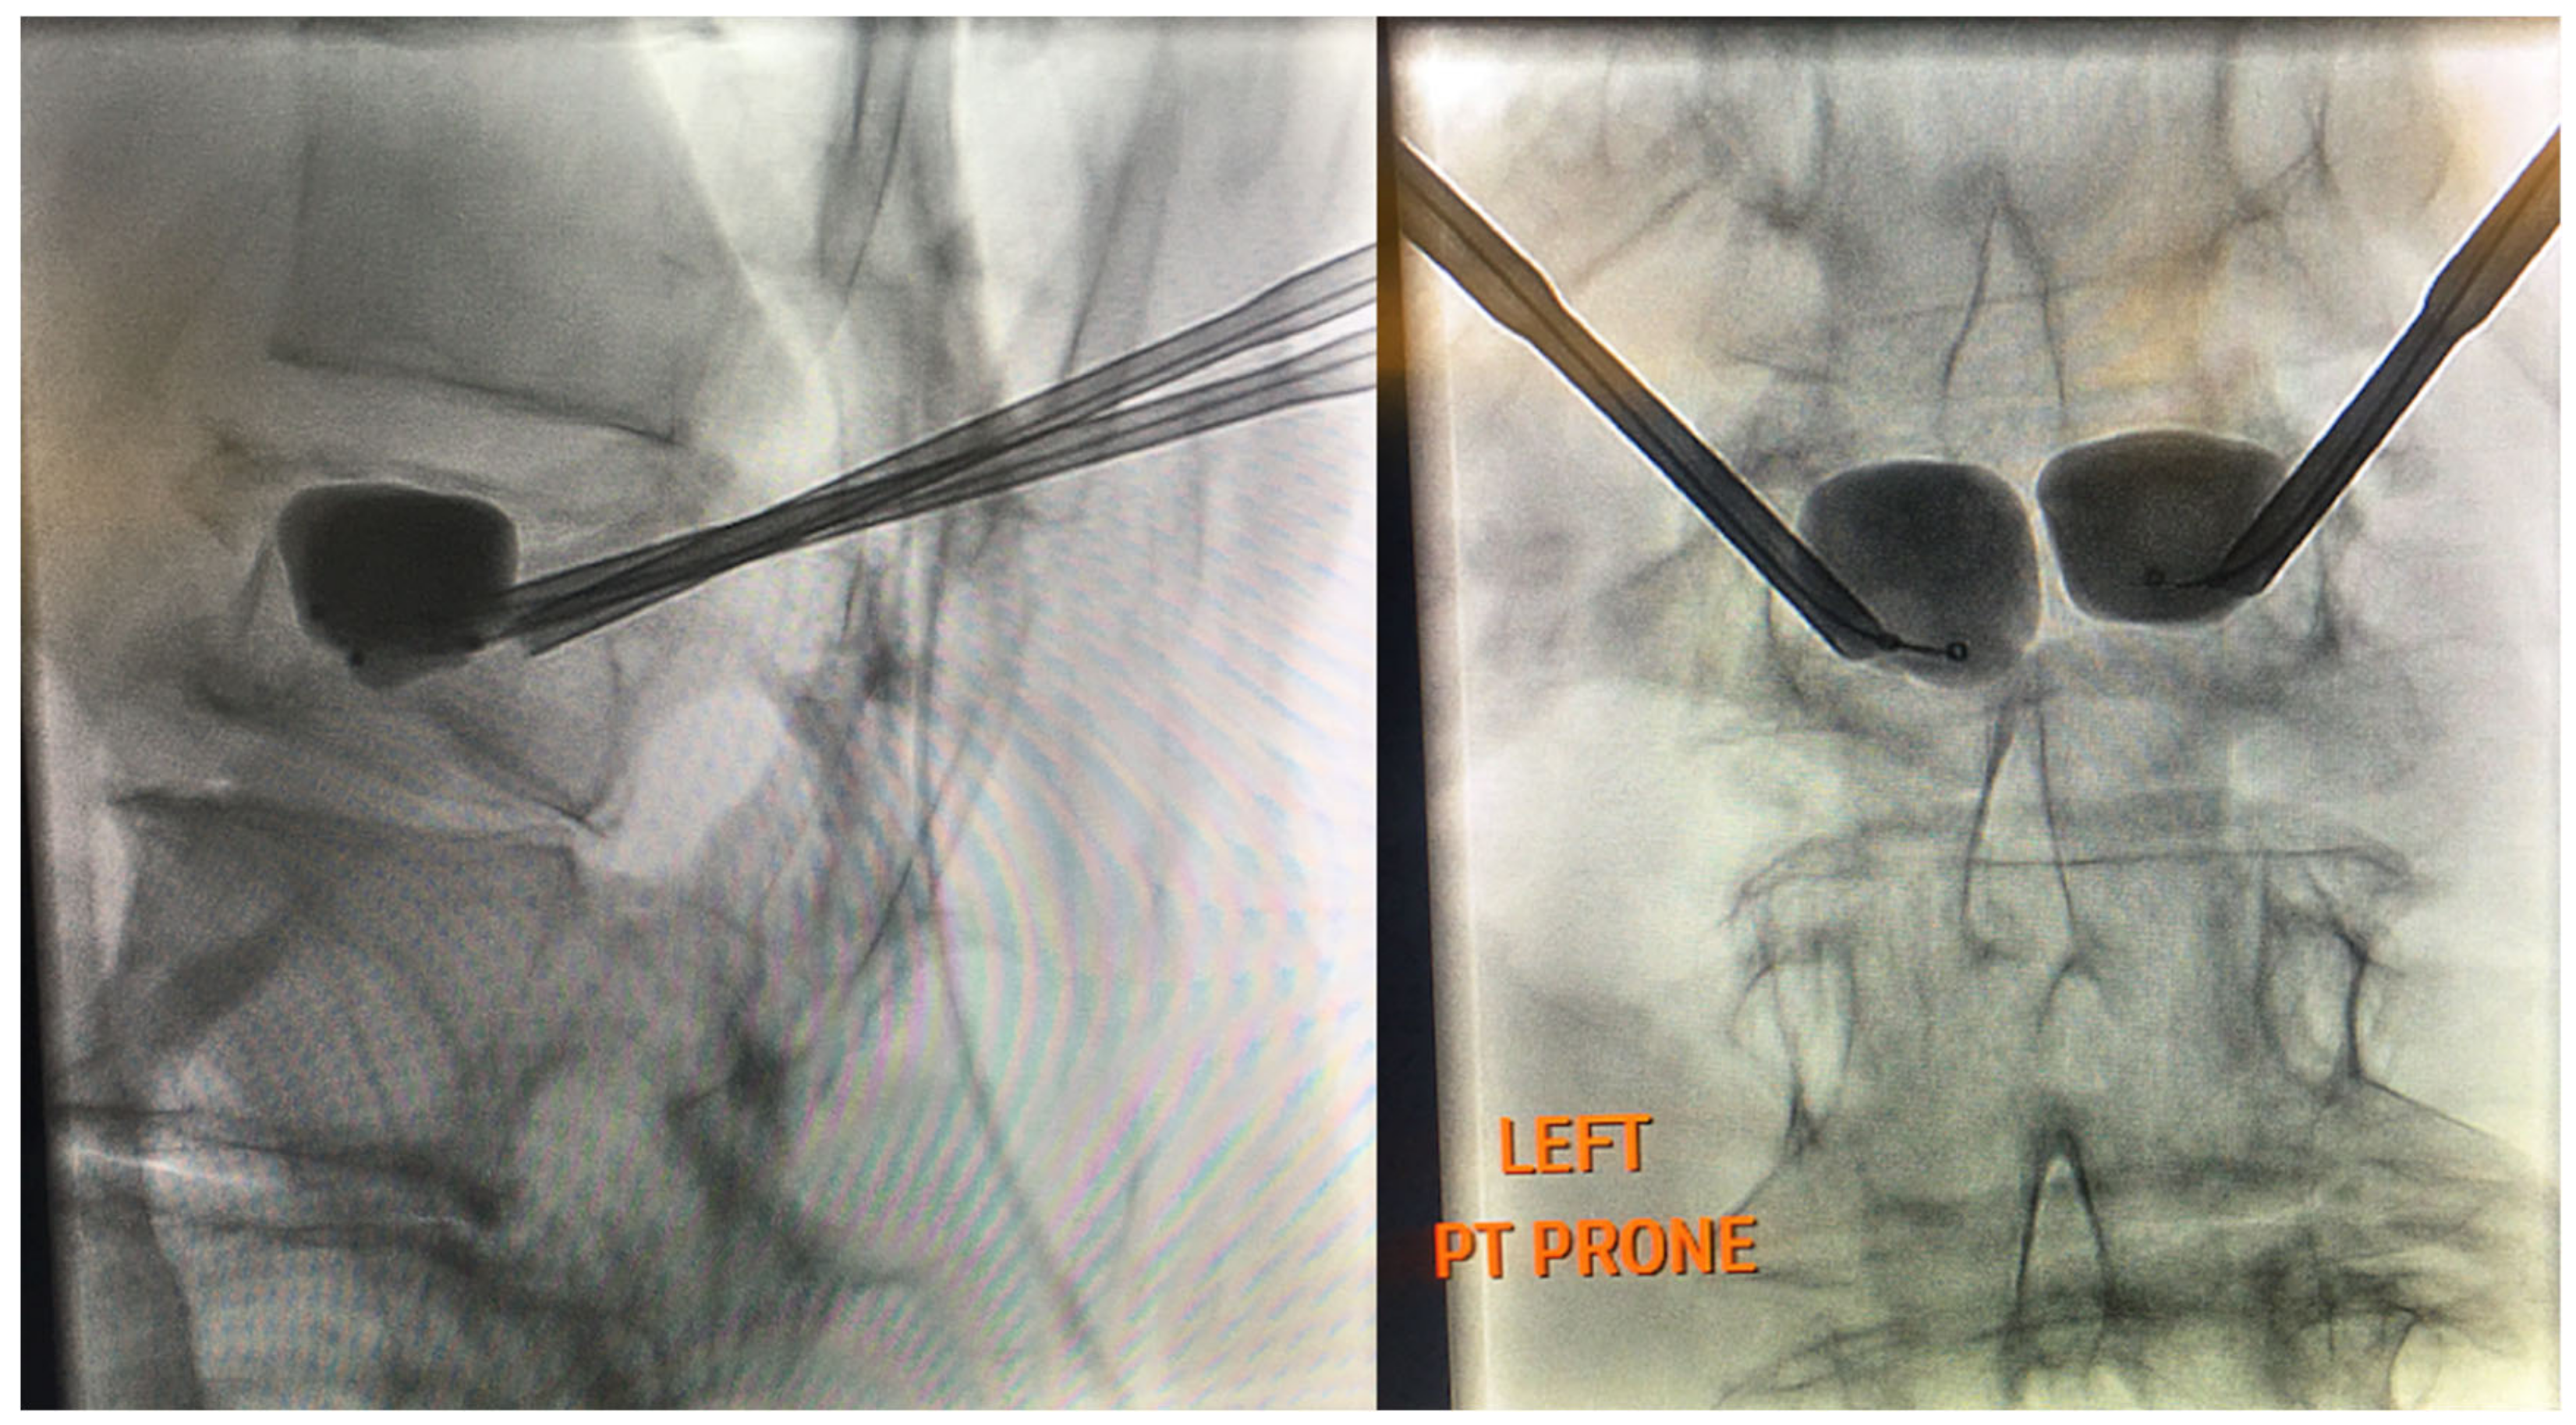

4.6. Basivertebral Nerve Ablation

- Nguyen, K.M.L.; Nguyen, D.T.D. Minimally invasive treatment for degenerative lumbar spine. Tech. Vasc. Interv. Radiol. 2020, 23, 100700. [Google Scholar] [CrossRef]

- Urits, I.; Noor, N.; Johal, A.S.; Leider, J.; Brinkman, J.; Fackler, N.; Vij, N.; An, D.; Cornett, E.M.; Kaye, A.D.; et al. Basivertebral nerve ablation for the treatment of vertebrogenic pain. Pain Ther. 2021, 10, 39–53. [Google Scholar] [CrossRef] [PubMed]

- Michalik, A.; Conger, A.; Smuck, M.; Maus, T.P.; McCormick, Z.L. Intraosseous basivertebral nerve radiofrequency ablation for the treatment of vertebral body endplate low back pain: Current evidence and future directions. Pain Med. 2021, 22, S24–S30. [Google Scholar] [CrossRef] [PubMed]

- Tieppo Francio, V.; Sherwood, D.; Twohey, E.; Barndt, B.; Pagan-Rosado, R.; Eubanks, J.; Sayed, D. Developments in minimally invasive surgical options for vertebral pain: Basivertebral nerve ablation—A narrative review. J. Pain Res. 2021, 14, 1887. [Google Scholar] [CrossRef] [PubMed]

- Kim, H.S.; Wu, P.H.; Jang, I.-T. Lumbar Degenerative Disease Part 1: Anatomy and pathophysiology of intervertebral discogenic pain and radiofrequency ablation of basivertebral and sinuvertebral nerve treatment for chronic discogenic back pain: A prospective case series and review of literature. Int. J. Mol. Sci. 2020, 21, 1483. [Google Scholar] [CrossRef] [Green Version]

- Kim, H.S.; Adsul, N.; Yudoyono, F.; Paudel, B.; Kim, K.J.; Choi, S.H.; Kim, J.H.; Chung, S.K.; Choi, J.-H.; Jang, J.-S.; et al. Transforaminal epiduroscopic basivertebral nerve laser ablation for chronic low back pain associated with modic changes: A preliminary open-label study. Pain Res. Manag. 2018, 2018, 6857983. [Google Scholar] [CrossRef] [PubMed] [Green Version]